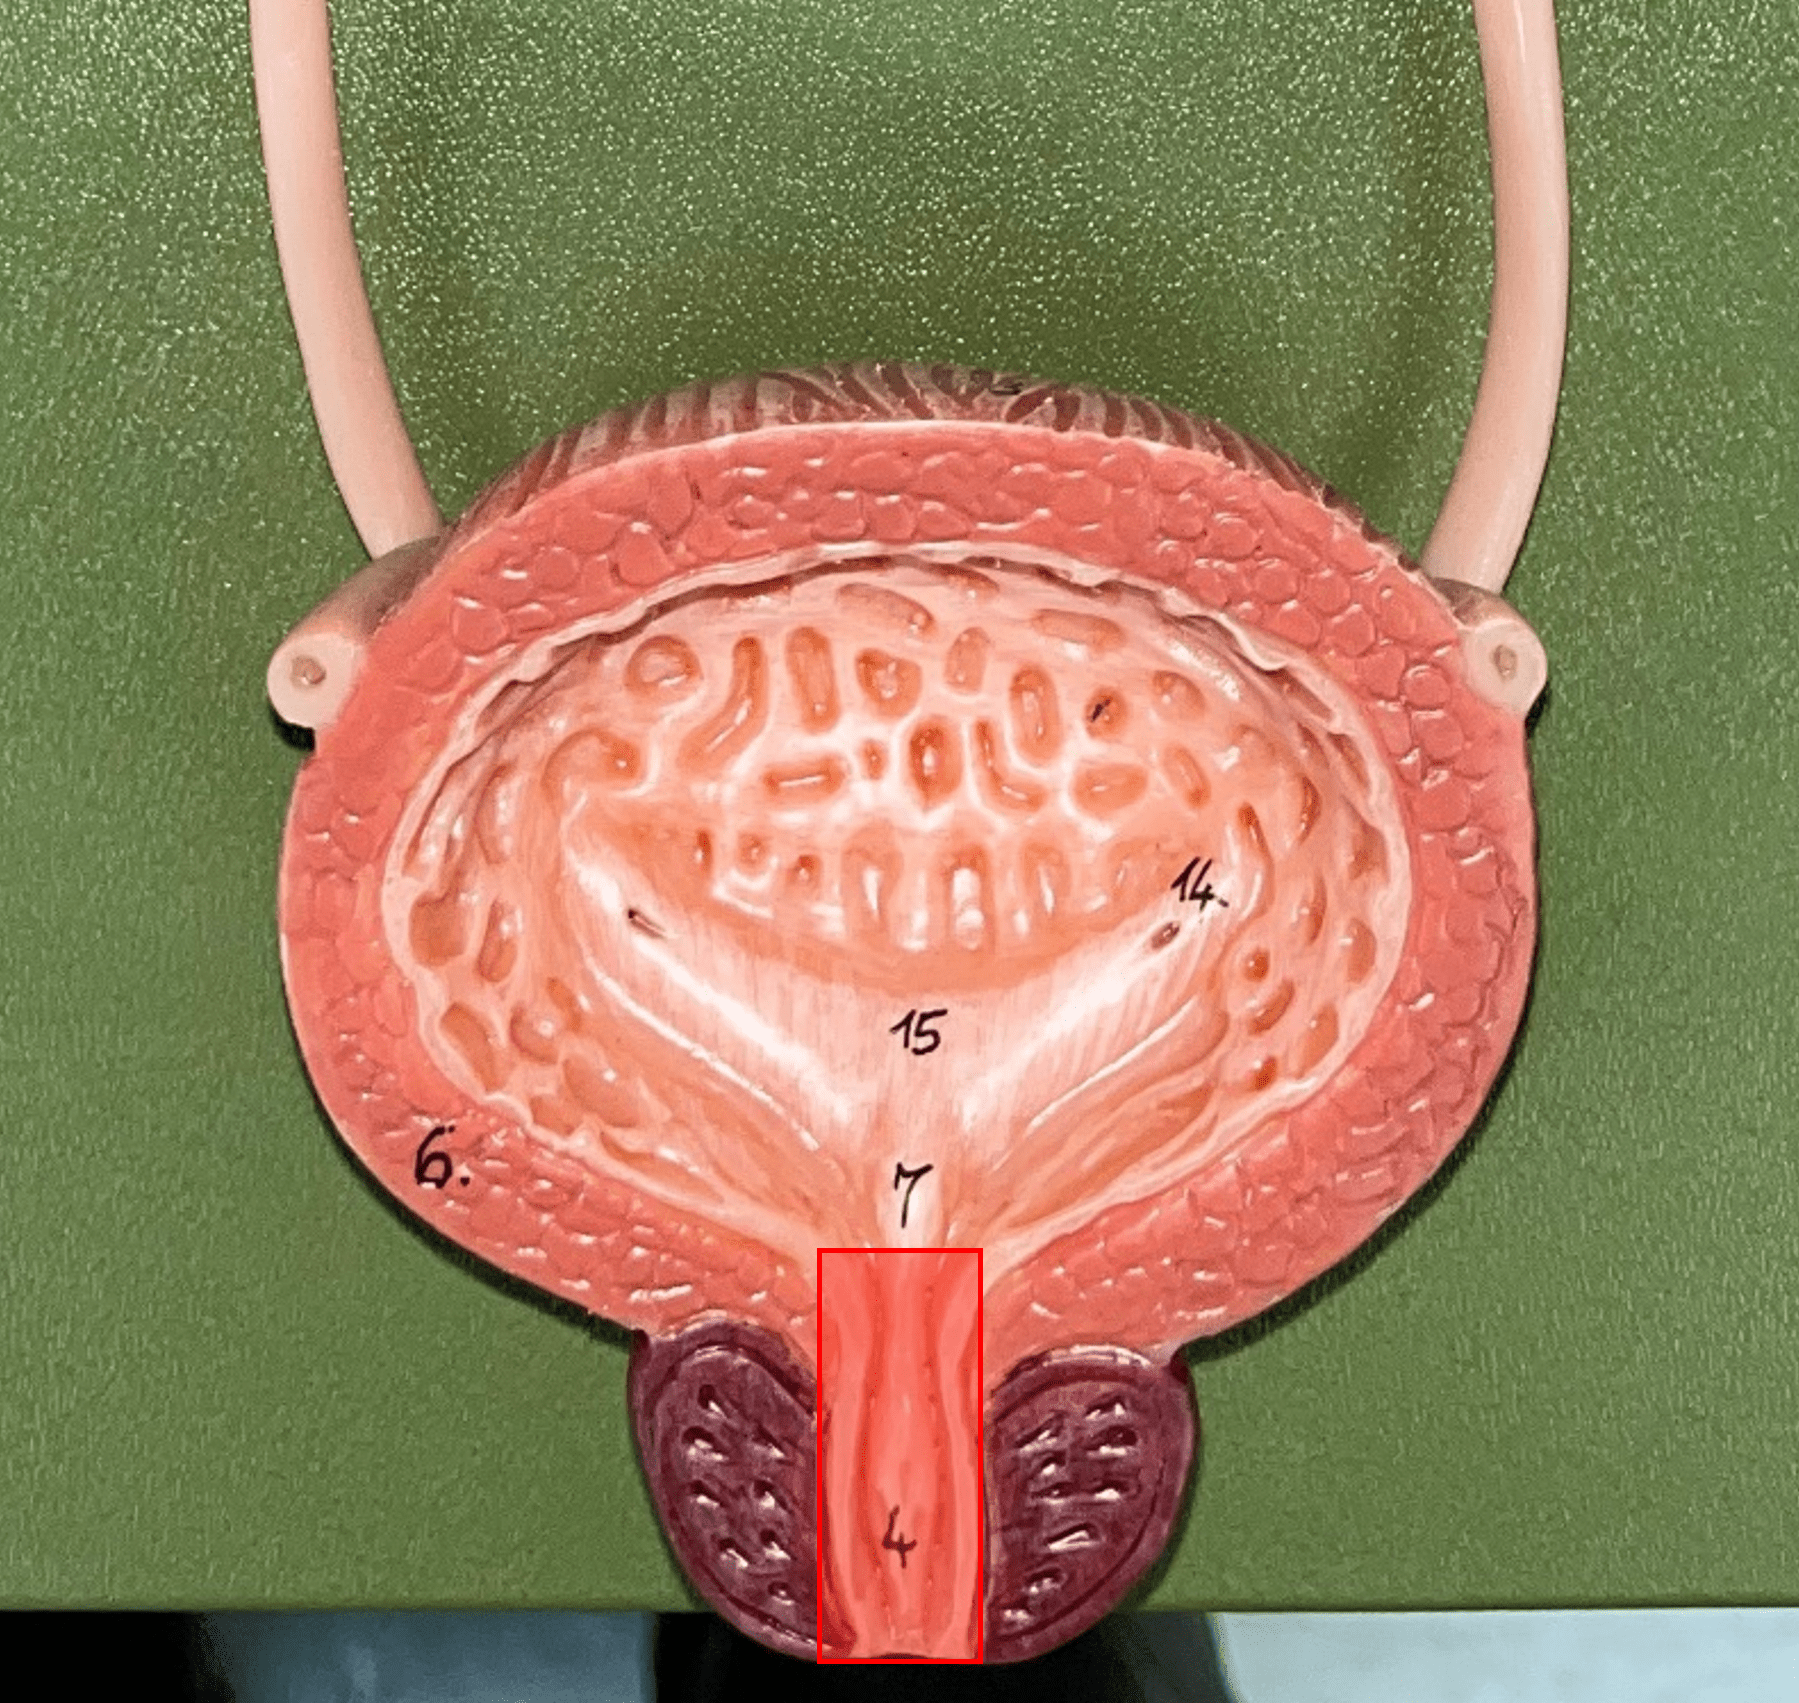

urinary bladder

The hollow sac organ that collects and temporarily stores urine.

rugae

• Part of the urinary bladder.

• Folds of the mucous membrane of the bladder.

• Flattens as the bladder fills with urine to increase capacity.

New cards

trigone

• Part of the urinary bladder.

• The triangle formed by the ureteral openings and internal urethra orifice.

New cards

ureteral opening

• Part of the urinary bladder.

• A posterior opening on either side of the of the bladder led in by the ureters.

New cards

internal urethral orifice

• Part of the urinary bladder.

• The anterior opening of the bladder leading to the urethra.

detrusor muscle

• Part of the urinary bladder.

• The muscularis of the bladder.

• Contracts to expel urine from the bladder.

urethra

A tubular organ carrying urine from the bladder to the exterior during micturition (voiding of urine).

New cards

external urethral orifice

• Part of the urethra.

• The opening of the urethra to the exterior.

New cards

internal urethral sphincter

\

• Part of the urethra.

• A circular layer of circular smooth muscle located just after the internal urethral orifice.

• Involuntary muscle allowing urine to flow outward.

New cards

external urethral sphincter

• Part of the urethra.

• A layer of skeletal muscle located just before the external urethral orifice.

• Voluntary muscle allowing urine to flow out to the exterior.